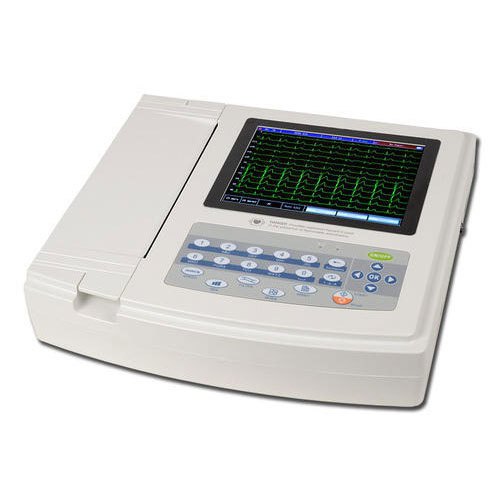

Bionet CardioTouch 3000 12 Channel ECG Machine

Bionet CardioTouch 3000 12 Channel ECG Machine

.jpeg) ECG 12 CHANNEL - MEDEXBIO

ECG 12 CHANNEL - MEDEXBIO

ECG MACHINE 6 CHANNEL - MEDEXBIO

ECG MACHINE 6 CHANNEL - MEDEXBIO

3 Channel ECG - MEDEXBIO

3 Channel ECG - MEDEXBIO

ECG MACHINE 12 CHANNNEL - INDIAN BRAND

ECG MACHINE 12 CHANNNEL - INDIAN BRAND

Digital 6 Channel ECG Machine

Digital 6 Channel ECG Machine

Yonker 7inch display 3 channel ECG Machine with touch screen

Yonker 7inch display 3 channel ECG Machine with touch screen

3 Channel 7 Inch Touch Screen Portable Electrocardiograph ECG Machine

3 Channel 7 Inch Touch Screen Portable Electrocardiograph ECG Machine

Zoncare 12 Channel ECG Machine

Zoncare 12 Channel ECG Machine

Edan ECG Machine SE-601 Series 6-Channel ECG

Edan ECG Machine SE-601 Series 6-Channel ECG

CONTEC ECG600G Digital 6 channel Electrocardiograph ECG machine EKG CE

CONTEC ECG600G Digital 6 channel Electrocardiograph ECG machine EKG CE

CONTEC ECG300G Electrocardiograph

CONTEC ECG300G Electrocardiograph

Yonker 7inch Display 3 Channel ECG Machine With Touch Screen

Yonker 7inch Display 3 Channel ECG Machine With Touch Screen

DAWEI 12Channel ECG Machine

DAWEI 12Channel ECG Machine

Dawei ECG Machine 3 Channel

Dawei ECG Machine 3 Channel

.jpeg) Comen – 12 Channel ECG Machine, CM1200

Comen – 12 Channel ECG Machine, CM1200

ECG 1200G – Contec

ECG 1200G – Contec

ECG 1212G – Contec

ECG 1212G – Contec

YKD MED ECG 3 CHANNEL

YKD MED ECG 3 CHANNEL

ECG 12 CHANNEL 3A CANADA

ECG 12 CHANNEL 3A CANADA